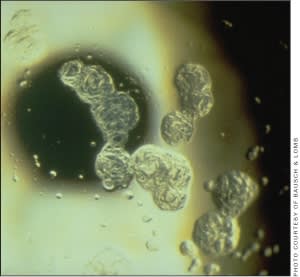

To add to the complex formation of biofilms, one must examine biofilms and their relationship to contact lens deposition. Lens wear causes changes in the structure of the tear film, particularly the lipid layer (Jenkinson, 1995). Silicone hydrogel lenses have differing chemistries compared to traditional HEMA-based lenses, and their hydrophobic surfaces deposit minimal amounts of protein and higher amounts of lipids (Lorentz, 2007). There have been early speculations that this may be significant in silicone hydrogel lens wearers (Ghormley, 2006) (Figures 1 and 2).

Figure 2. Lipid and protein deposition on soft lens surface.